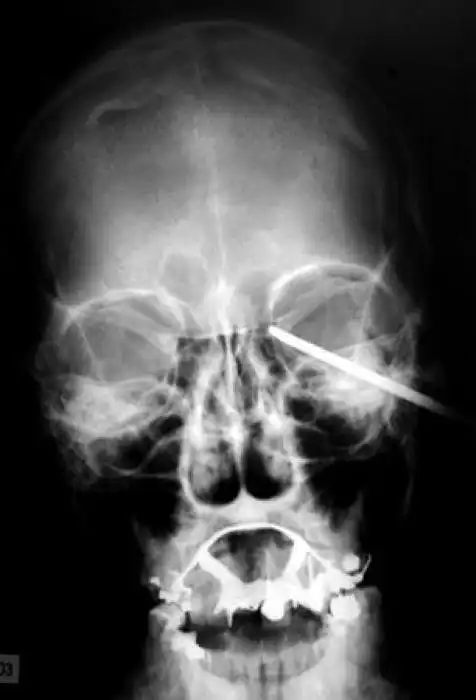

На рентгеновских снимках людей порой можно обнаружить самые необычные предметы, которые находятся в их теле.